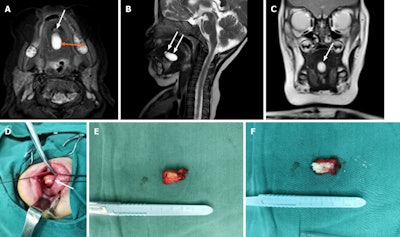

An intraoral approach was used to remove the cyst due its location near the supramylohyoid muscle. The size of the cyst prevented direct oral intubation, so clear fluid was withdrawn from the mass. She was given general anesthesia, and the cyst was removed. Three days after the surgery, a mild edema developed at the incision site and persisted despite three days of dexamethasone treatment, they wrote.

A week later, an MRI scan of the tongue revealed two small cystic lesions under the infant's tongue. One was about 0.8 x 1 x 0.5 cm, and the other was 1.2 x 0.5 x 0.5 cm. After reviewing the preoperative MRI, doctors identified a suspicious lesion of minute size that they believe they missed due to the larger cyst compressing it and doctors focusing on the most pronounced findings on the scan. After the sizable cyst was removed, the missed one grew rapidly. Nine days after surgery, the patient was discharged. An exam of the removed cyst showed it was a keratinizing stratified squamous epithelial lining complete with sebaceous adnexa, confirming it was a dermoid cyst, the authors wrote.

Nine months after surgery, the infant was brought back to the hospital. She had a normal mouth opening but her tongue was slightly raised. The doctor could feel a 2 x 2-cm mass on her tongue muscle near the midline in the floor of her mouth, and an MRI confirmed it. During the surgery to remove this cyst, doctors found another deeply embedded in the mylohyoid muscle at the floor of the mouth, which required careful separation. The content of these lesions was sebum, so they were diagnosed as dermoid cysts.